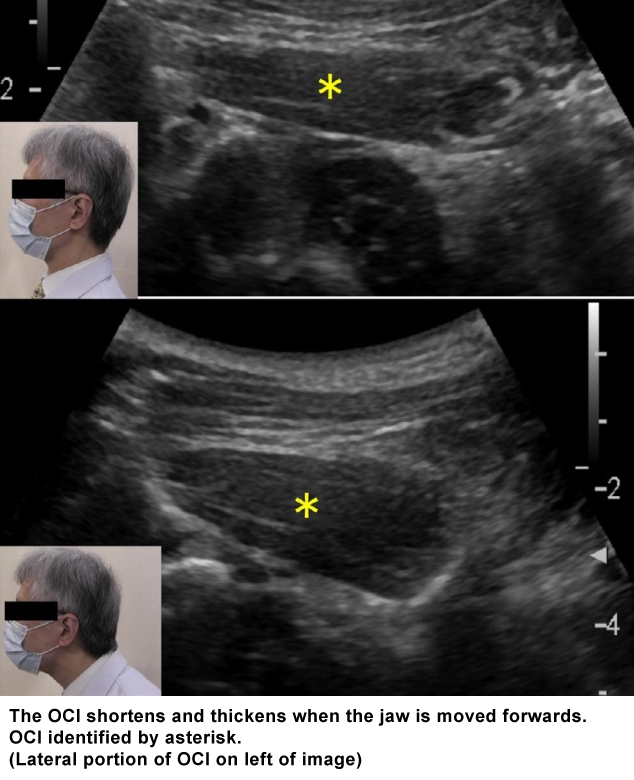

The almost horizontal obliquus capitis inferior (OCI) is inserted on the transverse process of the atlas and originates from the spinous process of the axis (C2). It contributes to head movement related to fast visual exploration.

The depth from the skin to the superficial fascia of the muscle ranges from about 10 mm to over 35 mm. The muscle thickness also has a wide degree of variability, ranging from 10 to 20 mm, and when it contracts, its thickness increases and the length shortens.

(vv)OCI.mp4(tt)